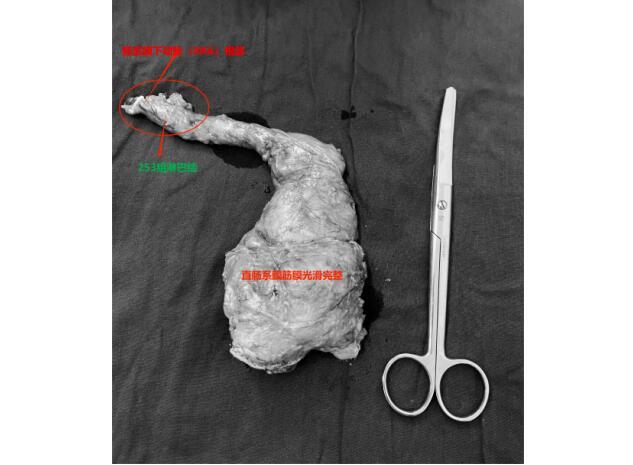

陈洪生教授凭借精湛的手术技巧和耐心细致的操作,在团队宝赛吉日呼主治医师、王中瑞住院医师的配合下,顺利通过腹腔镜完全经腹入路,自肠系膜下动脉左侧Toldt’s间隙-直肠后间隙-肛提肌上间隙,一直将直肠游离至直肠系膜终点,游离至肛提肌平面、括约肌间沟,将肿瘤提拉出肛提肌裂孔,从而获得了充足的下切缘,在保证肿瘤根治的基础上,顺利保住了肛门,同时保留了腹下神经和盆丛神经,最大程度保证术后肛门功能和排尿功能的恢复。手术层面十分清晰,观察肠管的血运良好,吻合确切。考虑到高龄患者日后再次进行手术和麻醉的风险,并没有进行保护性造口,而是留置了肛门减压管。在围手术期个体化、精细化管理下,术后第二日正常饮水,术后第五日开始进流食,在正常排便后逐步撤离了肛管和盆腔引流管,患者术后恢复良好,没有出现吻合口瘘,肛门的功能也保留完好。

81岁的周老(化名)因间断便血,肠镜检查发现直肠恶性肿瘤,肠镜及直肠核磁评估肿瘤距肛缘5cm,肿瘤的位置同样很低,患者及家属为求保肛手术治疗,慕名找到陈洪生教授。通过细致的术前评估和术前准备,在克服了男性骨盆狭窄等不利条件下,经过艰苦的努力,陈洪生教授团队再次成功实施了“腹腔镜完全经腹入路直肠括约肌间切除术(ISR)”,既切除了直肠的恶性肿瘤,又极限地保留了肛门和肛门的功能。